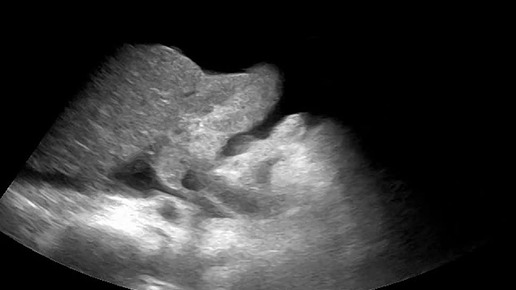

Видео к статье: "Свободная жидкость в брюшной полости"https://dzen.ru/a/Z-1KdOK-KyrjRiGF

Ультразвуковые находки от врача УЗД Зорина Я.П.